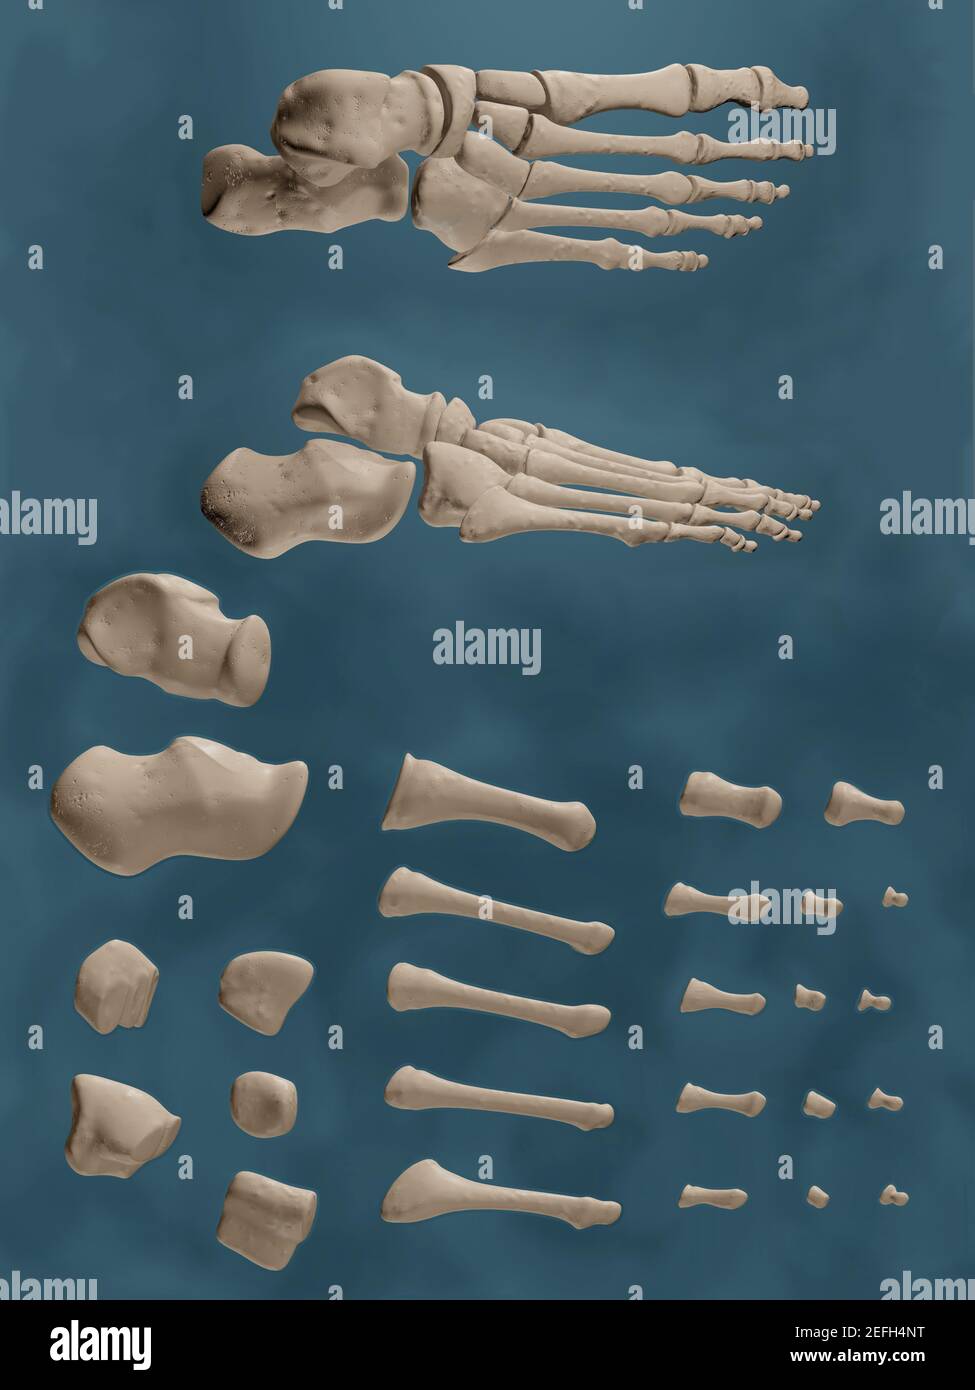

RF2EFH4NT–Affiche prête pour la salle de classe montrant les os du pied dans des vues anatomiques et éclatées.